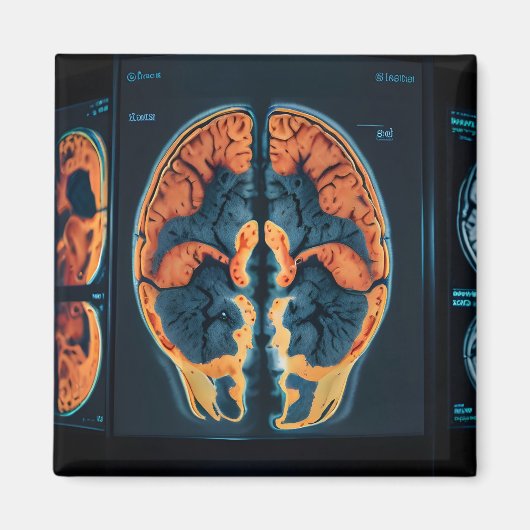

MRI hersenscan Magneet

MRI hersenscan